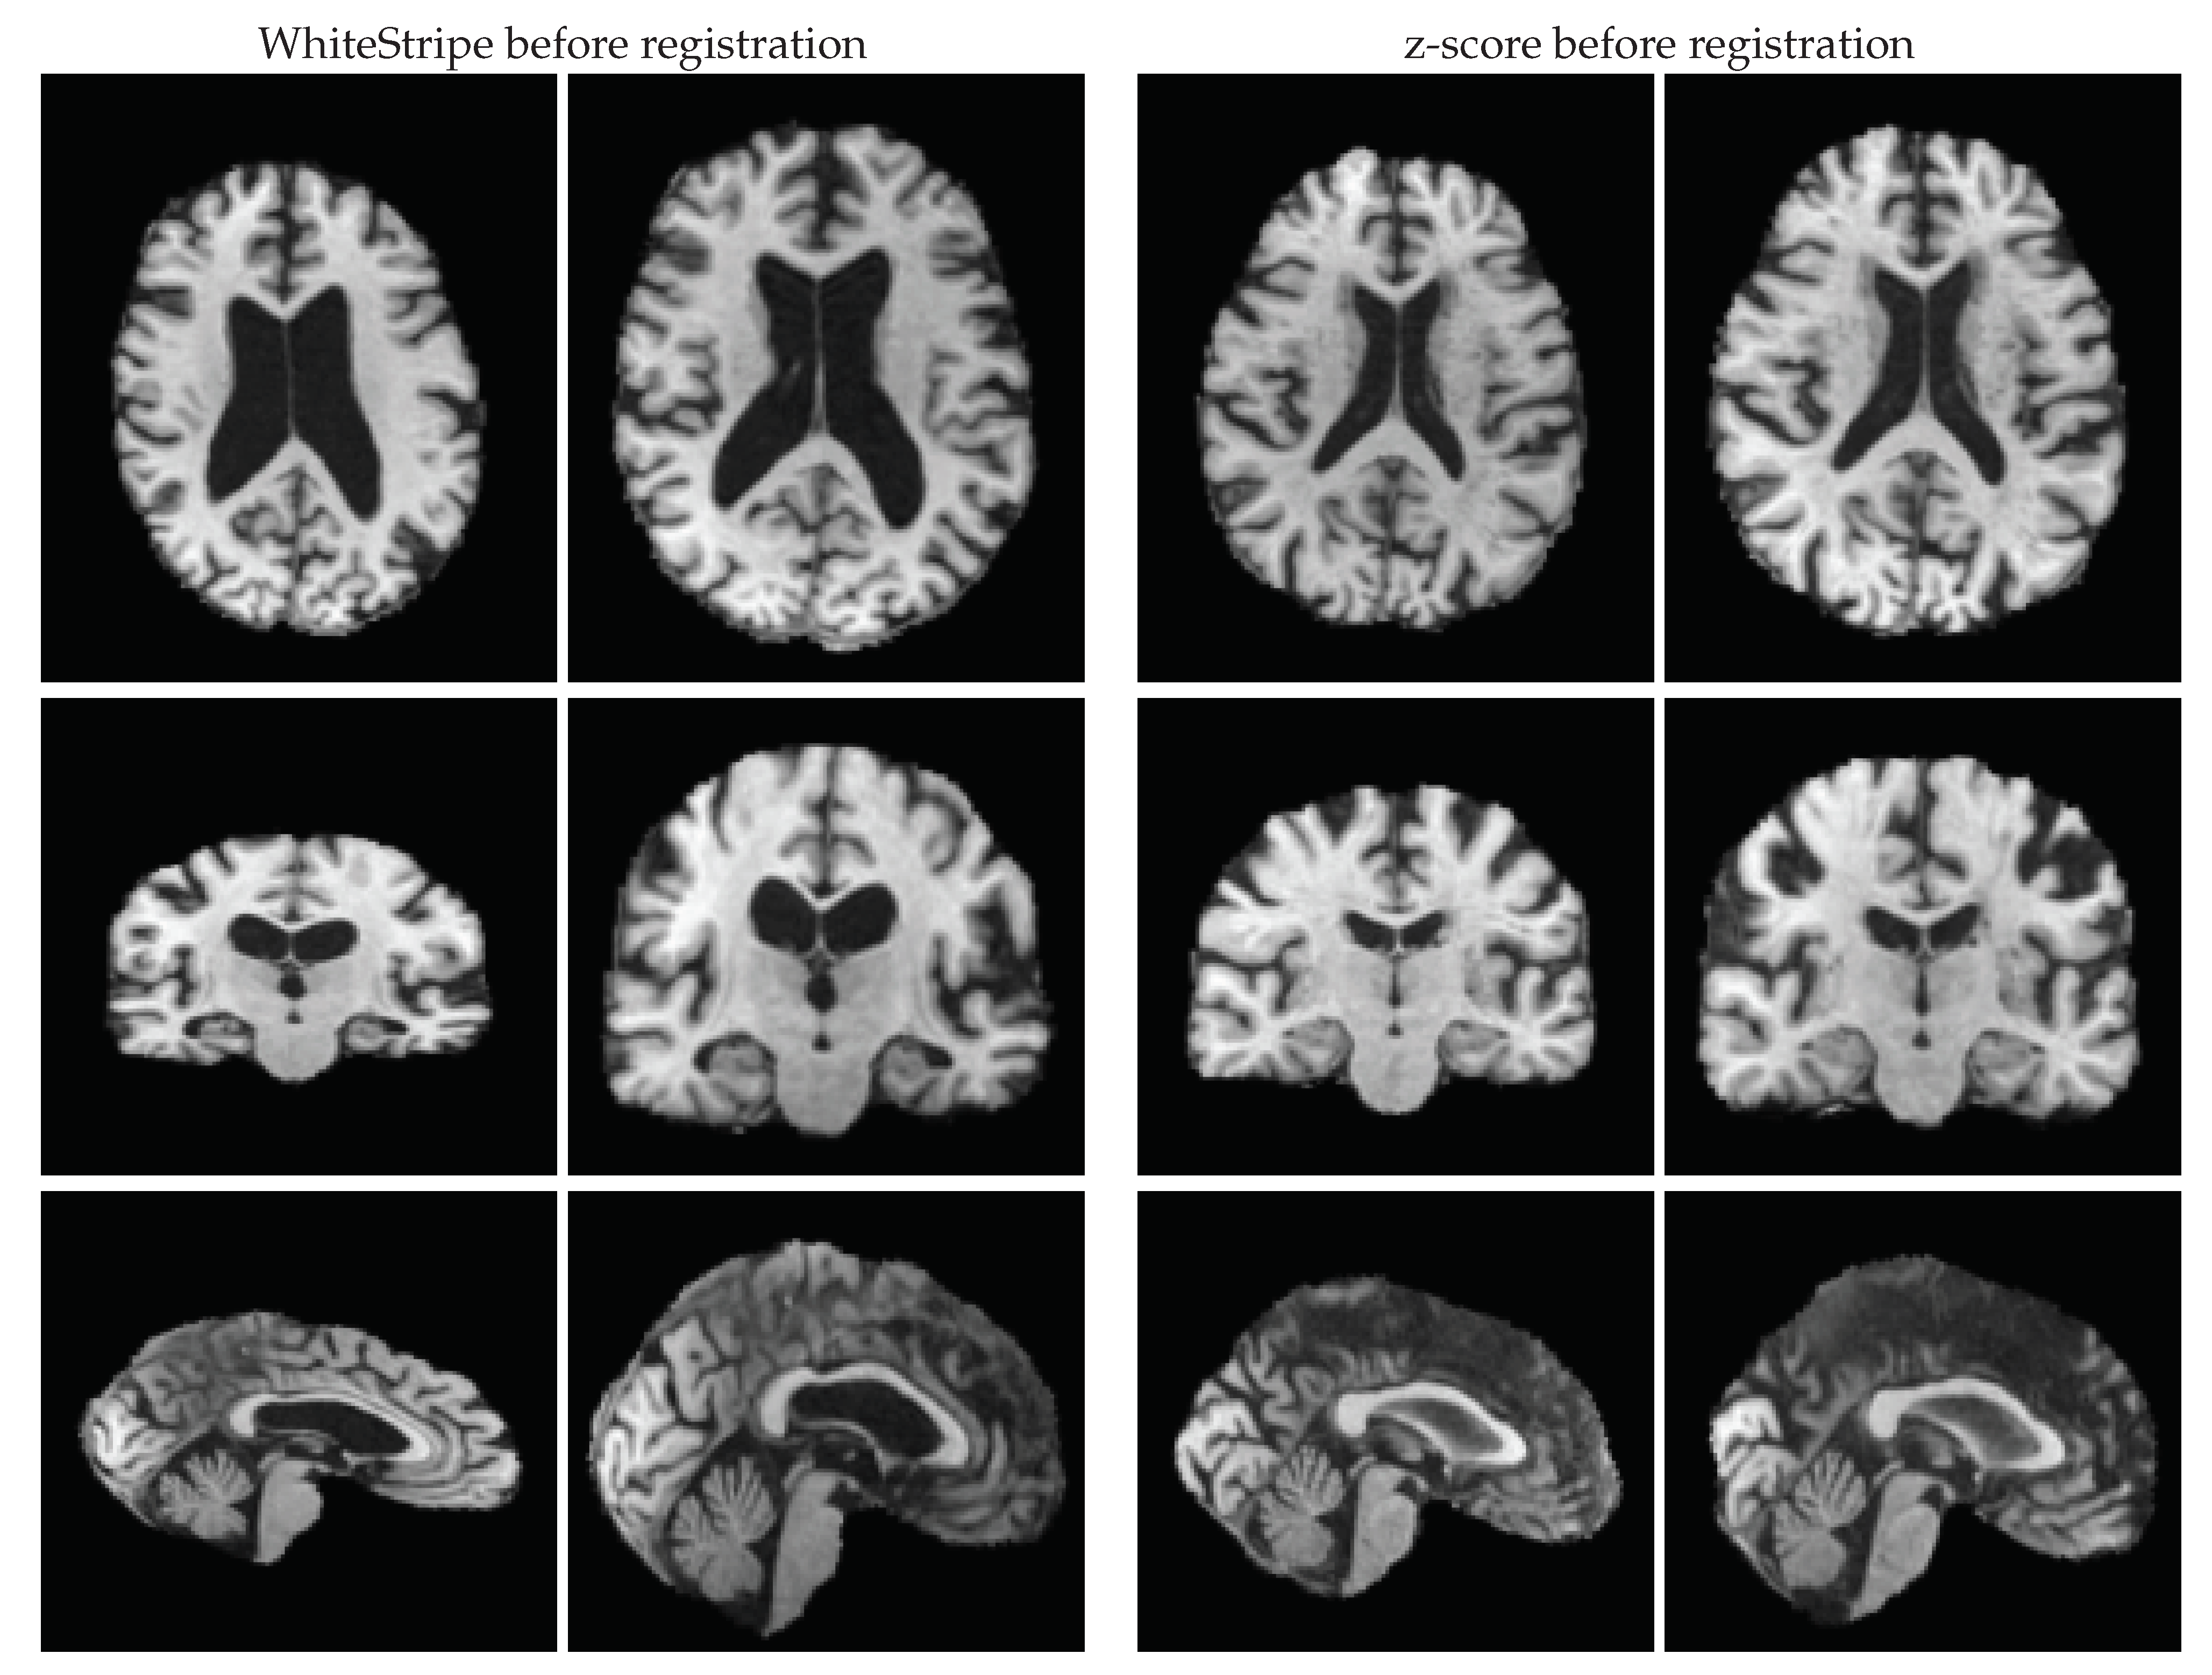

Estimated annual brain volume changes also differed depending on whether intensity standardisation was carried out or not. We noticed two clear trends in this regard. First, the application of histogram matching resulted in more similar estimates for both Alzheimer’s disease patients and normal control subjects, even more similar than those detected without standardisation. This situation may be reflective of a potential under-detection of the actual atrophy due to information loss (e.g., contrast loss) after the application of histogram matching. Second, standardising intensities with z-score and WhiteStripe before registering baseline and follow-up scans resulted in lower effect sizes compared to those obtained when applying them afterwards (z-score: 0.39 vs. 0.45 in OASIS and 0.27 vs. 0.45 in ADNI; WhiteStripe: 0.37 vs. 0.44 in OASIS and 0.02 vs. 0.46 in ADNI). After inspecting the registration outputs, we noticed that standardising with these two techniques prior to registration led to unsatisfactory outcomes in numerous cases (ADNI: 63 with WhiteStripe and 26 with z-score; OASIS: 24 with WhiteStripe and 44 with z-score). Some examples of this issue are shown in Figure 5. On the other hand, the application of these two techniques after registration led to some of the highest Cohen’s d values in both datasets.

Figure 5. Examples in which registration failed due to the application of WhiteStripe and z-score before registration. The cases correspond to “ADNI_005_S_0814” and “ADNI_098_S_0149” for which brain volume change was estimated around 2.89% and −5.02%, respectively.